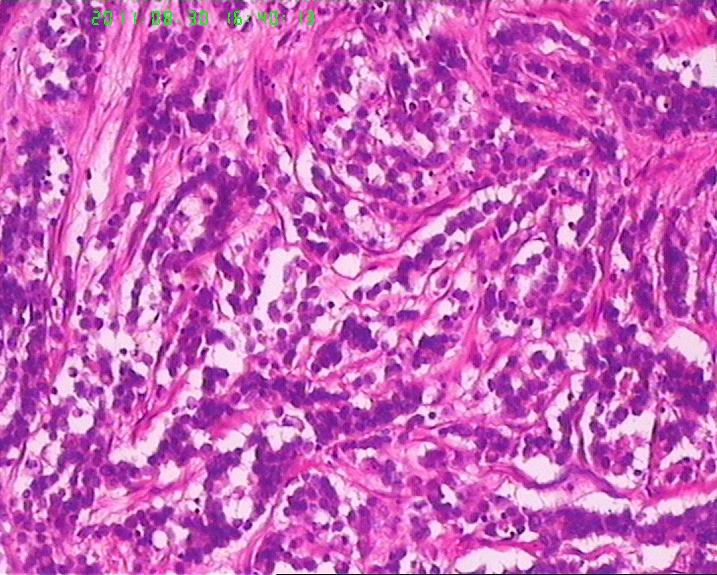

此例男,65岁。术前胃镜活检学生报告“低分化腺癌”,行手术治疗。术后见胃体后壁小弯测溃疡性肿物直径6.5cm,周围隆起质地硬,肉眼侵及肌层。镜下所见如图,似乎不是腺癌,是否是类癌??但核分裂很活跃,不见核仁。胃周淋巴结未检出转移。请老师们帮忙指正。学生感激。